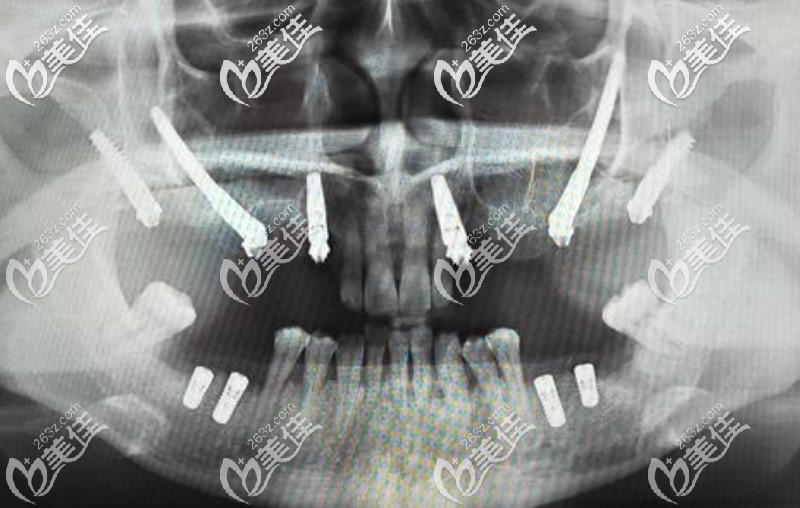

2、穿顴和穿翼種植技術

對于萎縮厲害的上頜骨萎縮使用顴種植體和穿翼板種植VIIV即刻負重技術,可以消除對骨移植的需求, 在手術后即刻修復,進行種植體負重,極大地改善了顧客對固定咬合的需求。好處是,治療周期短,并發(fā)癥相對少,植骨需求少。

穿顴穿翼種植牙示意圖▼